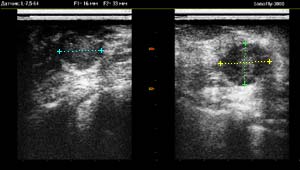

УЗИ ( ультразвуковая диагностика ) молочной железы позволяет свободно получать образы молочной железы в различных проекциях. На полученных изображениях хорошо просматриваются кисты - округлые полости, заполненные жидкостью, доброкачественные и злокачественные опухоли, различные дисплазии молочной железы. Ультразвуковое исследование является как самостоятельным методом выявления доброкачественных и злокачественных образований, так и дополнительным, применяемым в совокупности с рентгеновской маммографией. В ряде случаев ультразвук превосходит маммографию - при исследовании плотных молочных желез у молодых женщин; у женщин, имеющих фиброзно-кистозную мастопатию; в выявлении кист. Кроме того, ультразвуковые сканнеры используются для динамического наблюдения за уже выявленными доброкачественными новообразованиями молочной железы, чтобы определить, не произошло ли каких-либо изменений. Во время беременности и в период кормления грудью, ультразвук является ведущим методом исследования молочных желез.

Использование высокочастотного датчика обеспечивает достаточную разрешающую способность для определения образований даже малого размера.

Эта дата впоследствии автоматически вносится в протокол обследования и помогает оценить соответствие структуры тканей молочной железы дню цикла. Для маммографического УЗИ важной задачей является дифференциация кистозных и фиброзных образований. Наряду с другими методами, аппарат для ультразвуковой диагностики (УЗИ) SonoFly-3000 позволяет проводить построение яркостных гистограмм по любому сканируемому участку. Специфика распределения интенсивности в таких гистограммах помогает судить о природе образования.